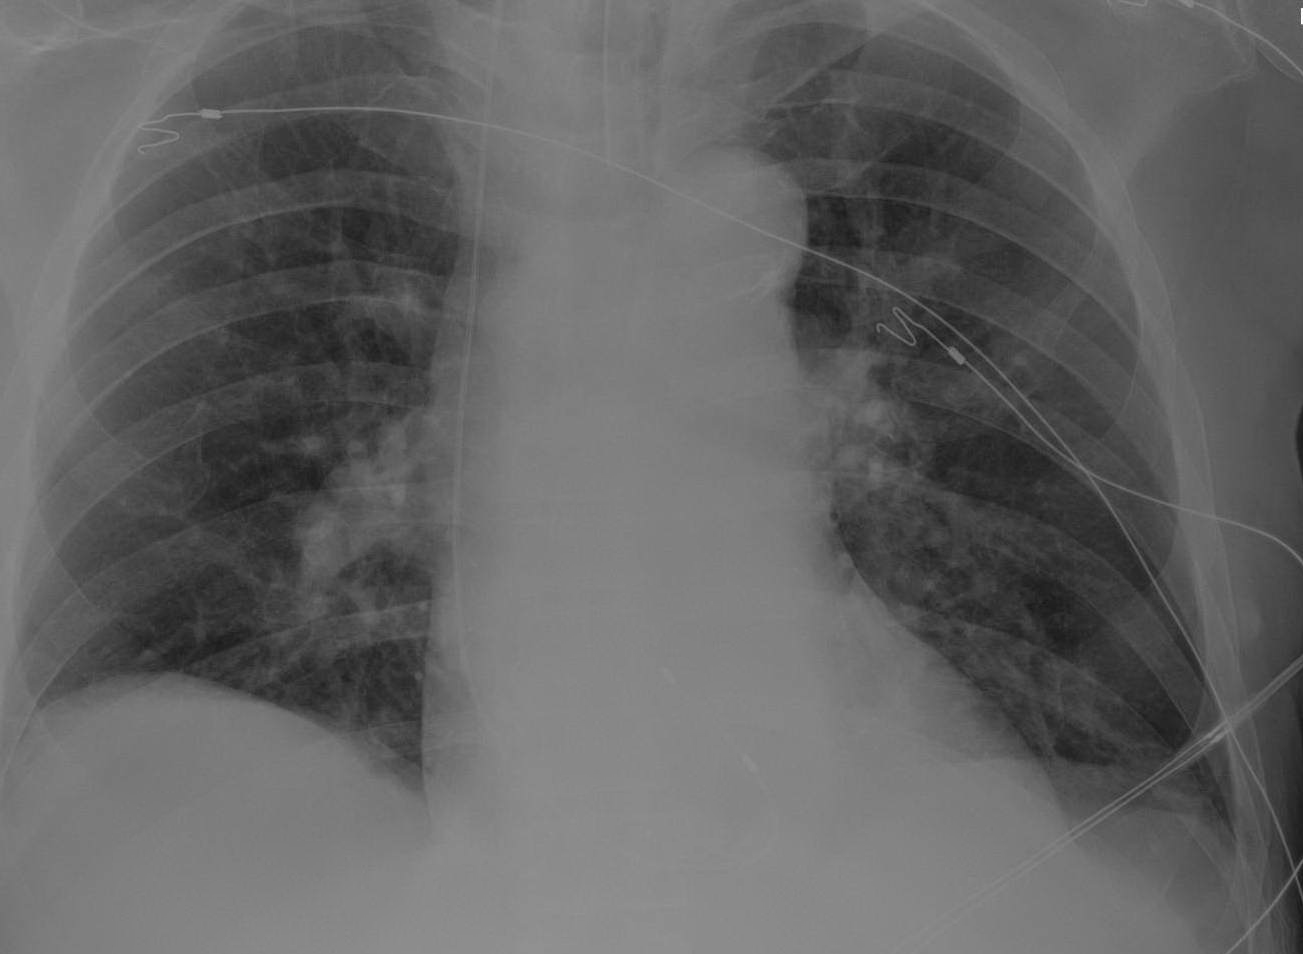

From www.radiology.expert

Chest Xray ICU Rv Chest X Ray right ventricle (rv) failure is usually the result of long standing lv failure or pulmonary disease and causes increased systemic venous pressure resulting. right heart strain (or more precisely right ventricular strain) is a term given to denote the presence of right ventricular dysfunction usually in the. the right ventricle (rv) is the most anterior of the. Rv Chest X Ray.